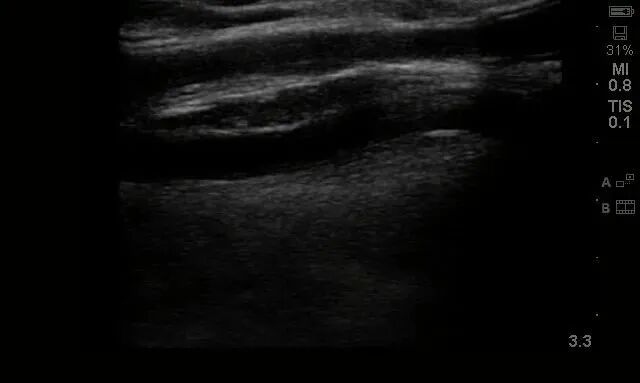

患者來院后,醫(yī)生為其查體,左上臂為人工血管動(dòng)靜脈內(nèi)瘺術(shù)后,觸診可及“U”型人工血管內(nèi)瘺成條索狀,質(zhì)硬,無法觸及震顫及聽及血管雜音,考慮人工血管動(dòng)靜脈內(nèi)瘺急性閉塞。而急診彩超也提示:人工血管內(nèi)充滿血栓,無血流,同時(shí)合并回流貴要靜脈狹窄(圖1、圖2),遂收住院擬行動(dòng)靜脈內(nèi)瘺經(jīng)皮球囊擴(kuò)張血管成形術(shù)+血栓取栓術(shù)。

圖2:術(shù)前回流貴要靜脈-人工血管吻合口處狹窄并血栓形成